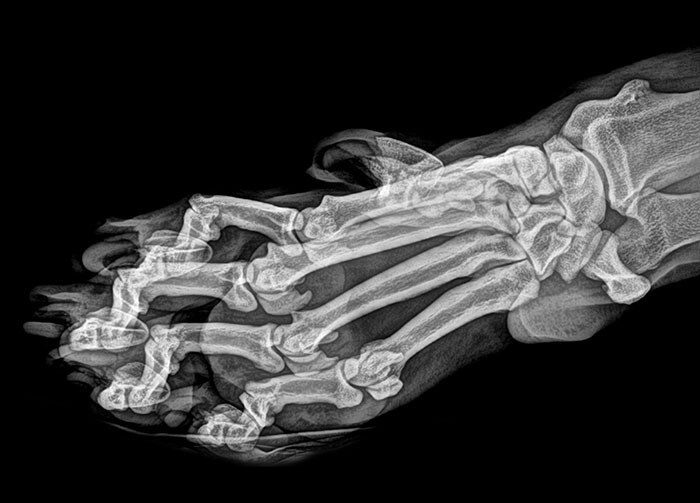

Ревматоидный артрит

Рентген женской стопы на шпильке